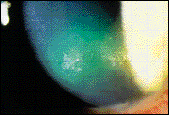

Slit lamp examination revealed two small epithelial defects in the lower third of the cornea surrounded by diffuse epithelial edema (Figure 2). There appeared to be no corneal involvement below the epithelium. The anterior chamber OS had 1+ cells, and the pupil responses were normal. Visual acuity with glasses was OD 20/20, OS 20/40. The patient was treated with appropriate antibiotics and asked to return the next day for follow-up.

Figure 2. Epithelial defects secondary to the lens fracture